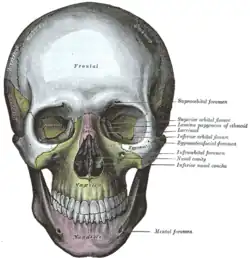

Crânio visto de frente.

Crânio visto de frente. -